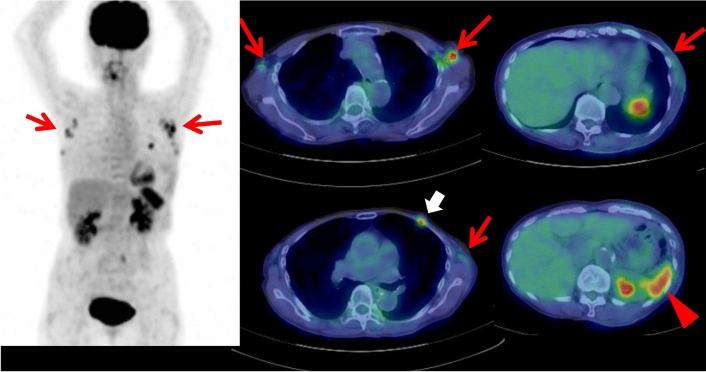

Fig. 5.

A 54-year-old male with dermatomyositis and interstitial pneumonia has been treated with corticosteroid. Whole-body FDG PET maximum projection image did not show increased FDG uptake in the systemic muscles probably due to the treatment effect. Cross-sectional FDG PET/CT images showed slightly increased FDG uptake (SUVmax 1.7) in the lung nodule of the right lower lobe (arrowhead), and focal FDG uptake (SUVmax 3.2) in the ascending colon which was diagnosed as colon cancer by endoscopic resection (arrow). Later, this patient had surgery of the right lung tumor of adenocarcinoma